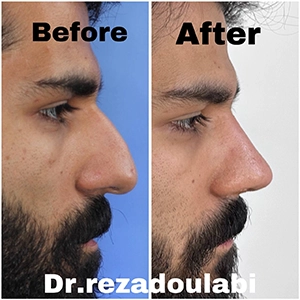

🎯 انتخاب بهترین جراح بینی در تهران

اگر به دنبال بهترین جراح بینی در تهران هستید، تجربه، نمونه کارهای موفق، ارتباط حرفهای با بیمار و آشنایی با تکنیکهای مدرن جراحی، معیارهایی مهم برای انتخاب شما هستند. حتماً عکسهای قبل و بعد عمل بینی بیماران را ببینید و در جلسه مشاوره تمام انتظارات خود را مطرح کنید.